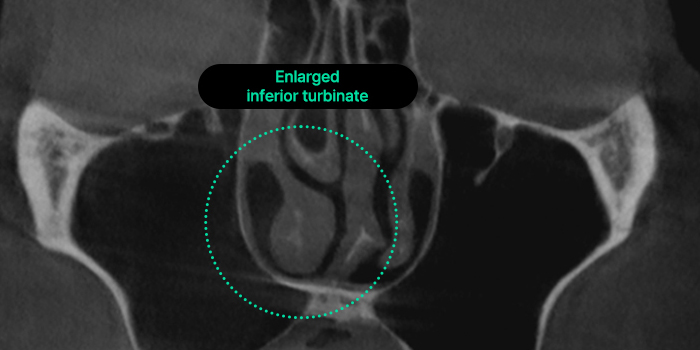

Hypertrophic Rhinitis

A result of chronic rhinitis, this condition deforms

the internal nasal structure, causing symptoms

such as nasal obstruction, snoring, and chronic

headaches. Allergic rhinitis may also accompany

it, where the nasal mucosa overreacts to certain

substances, leading to symptoms like runny

nose and nasal congestion.

Inflammation in the nasal mucosa, specifically

in the ‘inferior turbinate,’ causes it to enlarge,

resulting in nasal obstruction and loss of smell.